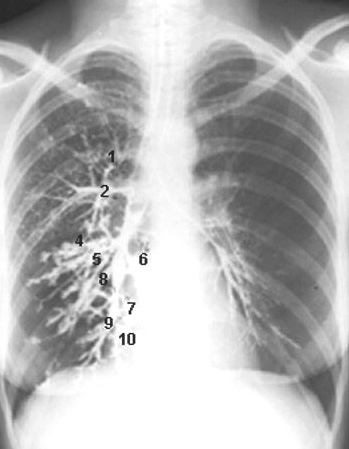

Les quatres posisions radiographiques de

base du thorax en position AP , PA (

postero-anterieur) , apico lordotique et profile

gauche . La distance trancissable etre 1,2 -

1,4m et le foyer central du rayon en place à T7 ou

au milieu de la ligne de deux bord inferieure de

l'omoplate |

Standard cliche de

radiographie de face ( PA ) et de profile gauche du

poumon .en position debout |

|

Avec les deux cliches OAG et OAD a angle

precedent , on peut detecter la lesion marquee en outre de

l'ombre du coeur et de la colonne vertebrale . Et par la meme

technique ,

quelques courbures de la silhouette du coeur avaient aussi detecte ... |